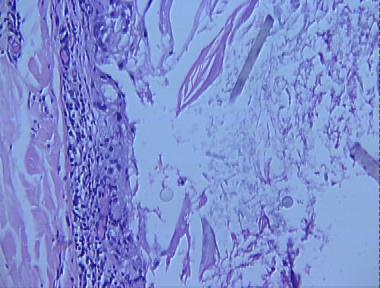

eruptive vellus hair cyst

Histologic Features